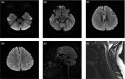

Acute disseminated encephalomyelitis (ADEM) is an autoimmune demyelinating disorder of the central nervous system and can present following influenza A infections as multifocal neurological deficits. ADEM remains a challenging diagnosis, and high clinical suspicious coupled with laboratory investigations and neuroimaging is required to exclude other primary and secondary demyelinating disorders.